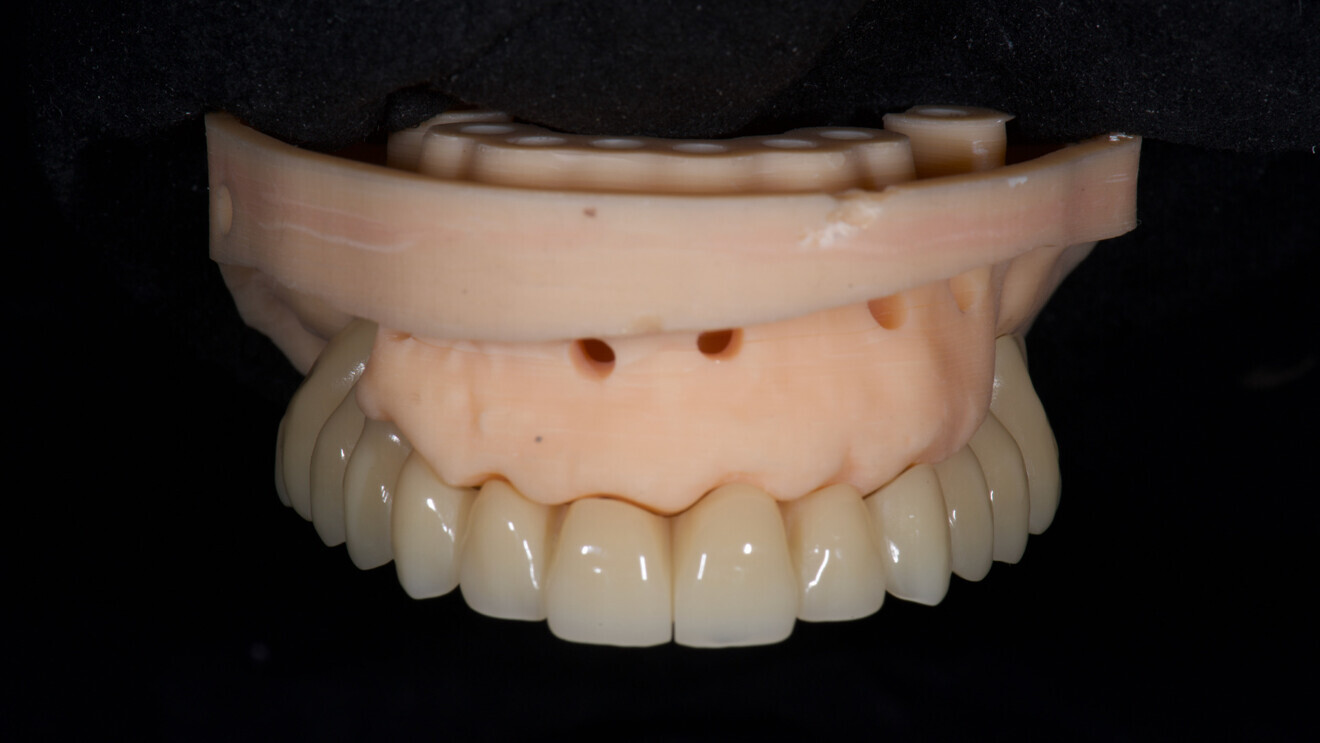

At the second appointment, a PMMA prototype supported by a metal bar was tested for aesthetic and functional accuracy. Passive fit of the metal framework was assessed using the one-screw (Sheffield) test and tactile verification with a dental explorer (Figs. 15–17a–f).15, 16

At the final appointment, the definitive hybrid screw-retained prosthesis was delivered. The definitive prosthesis consisted of a CAD/CAM titanium framework screwed on to all of the implants and three monolithic zirconia prosthetic segments bonded on top (Figs. 18a–c). The occlusion was evaluated, and the patient was enrolled in a four-month maintenance programme. At the last follow-up (one year after implant placement), all of the implants were successful and the patient was fully satisfied with the new prosthesis (Figs. 19–22).